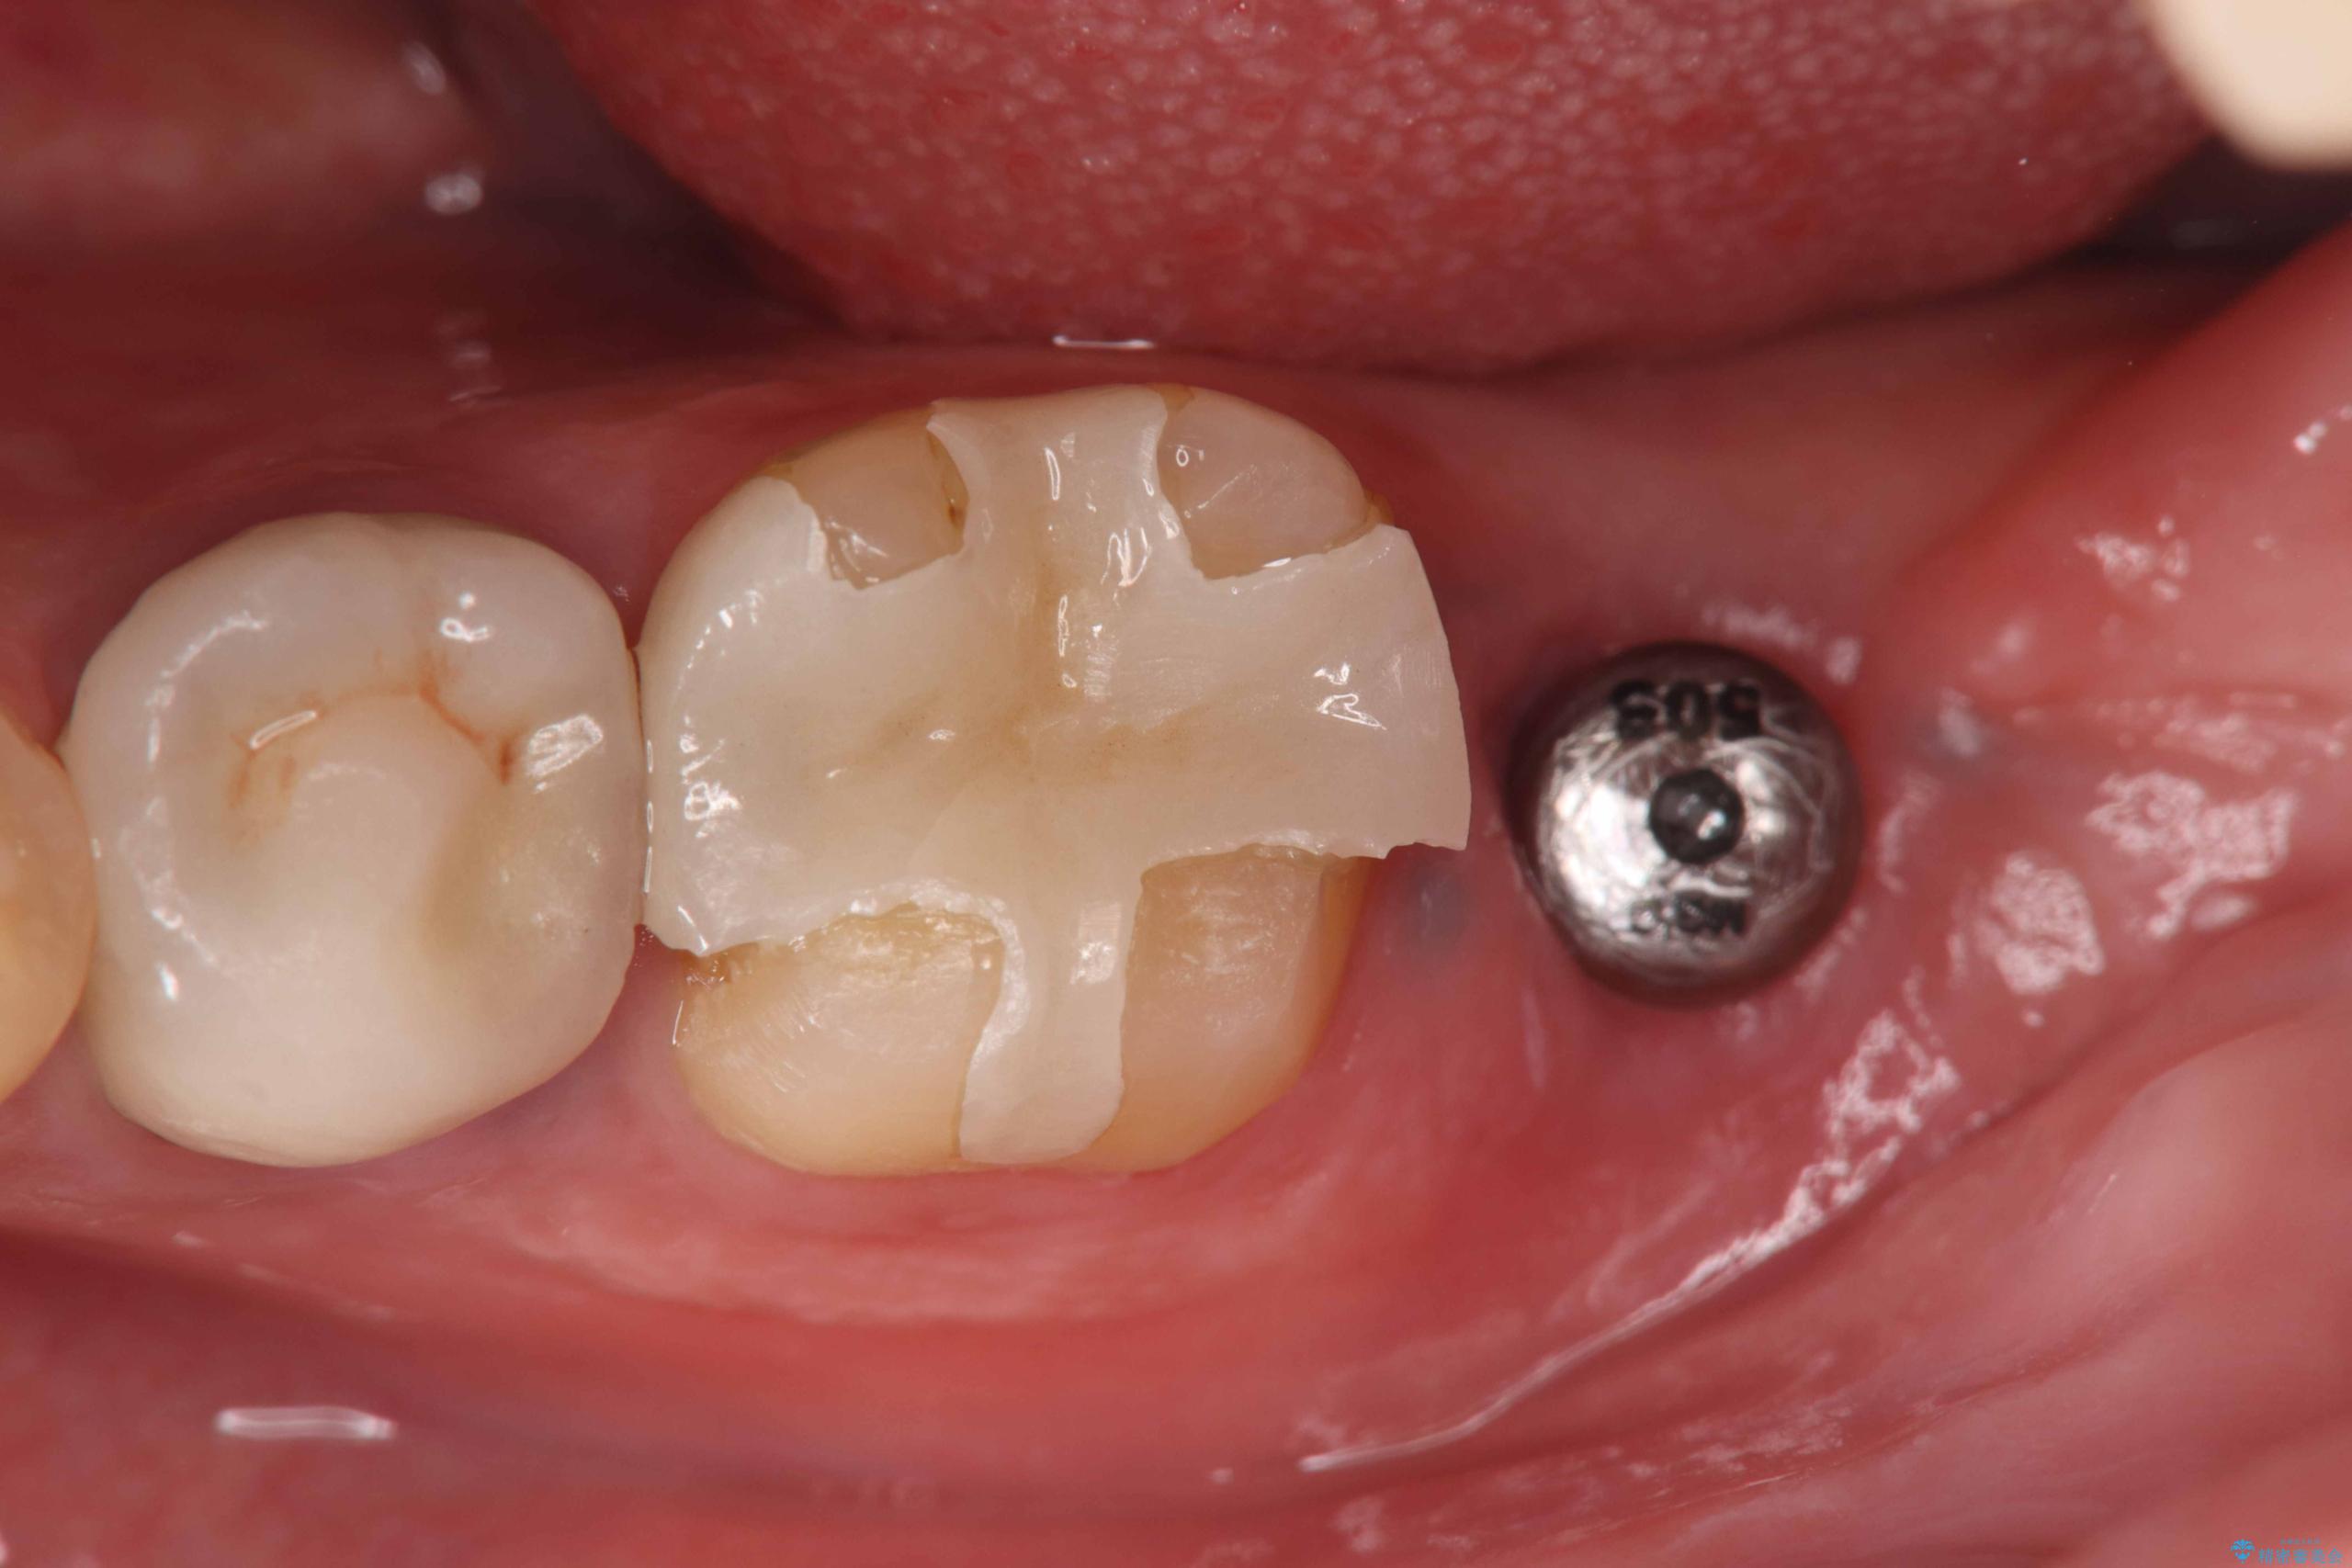

- 過去にヘミセクションが行われていたと思われる左下7番は、大きな歯根嚢胞および根尖病変が認められ、さらに骨縁下カリエスを伴っており、歯肉には瘻孔が形成されている状態でした。

保存は困難と判断し、左下7番は抜歯即時インプラントによる治療を行いました。

また、左下6番には形態が不自然で適合不良のセラミックインレーが装着されていたため、二次カリエスのリスクを考慮し、オールセラミッククラウンによる治療を行いました。